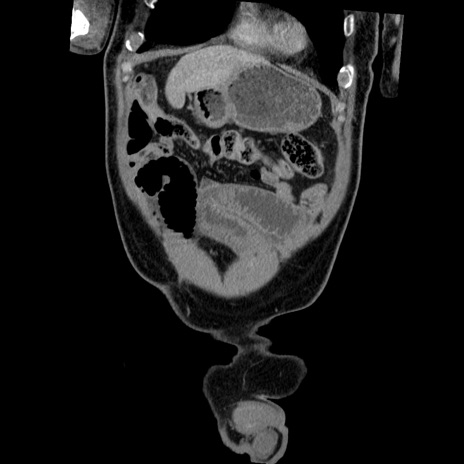

横断像

【症例】50歳代男性

【主訴】腹痛

【現病歴】AVMからの被殻出血のため回復期リハ病棟入院中。 本日午後3時頃急に下腹部痛が出現した。

【既往歴】AVM、被殻出血、虫垂炎、高血圧

【身体所見】意識晴明、左半身不全麻痺、会話の理解は良好、36.5°C、腹部:膨隆、全体に板状硬、下腹部正中に圧痛点あり、反跳痛-、筋性防御不明、右下腹部にope scar

【データ】WBC 9400、CRP 0.06